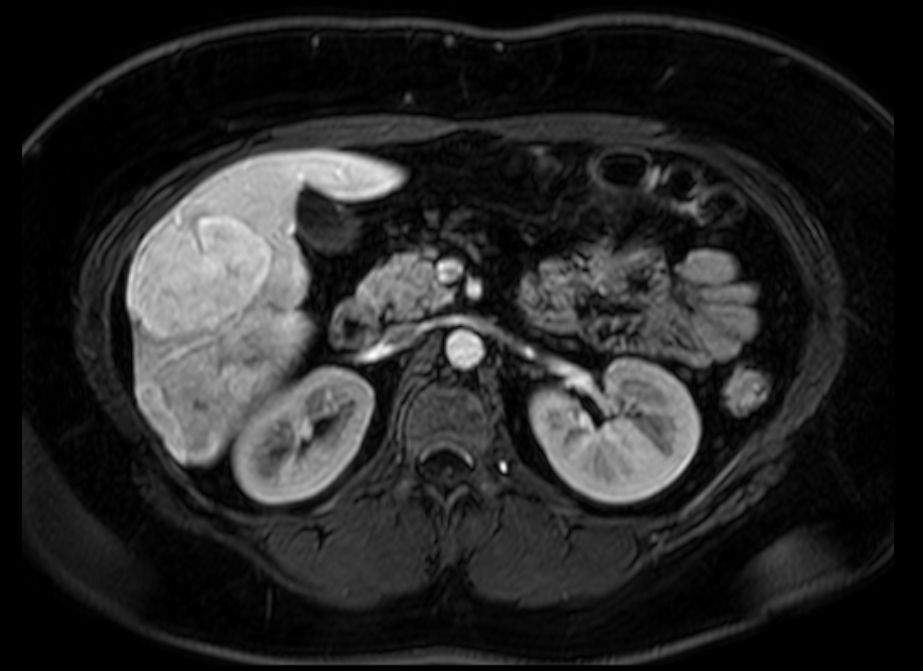

| Fall-Beispiel | 29-jährige übergewichtige Frau, die wegen Diarrhoe zur Aufnahme kam. Bei der Sonographie des Abdomens fiel eine Raumforderung der Leber auf. Das MRT zeigt mehrere Herdbildungen, die gut abgegrenzt sind. | ||